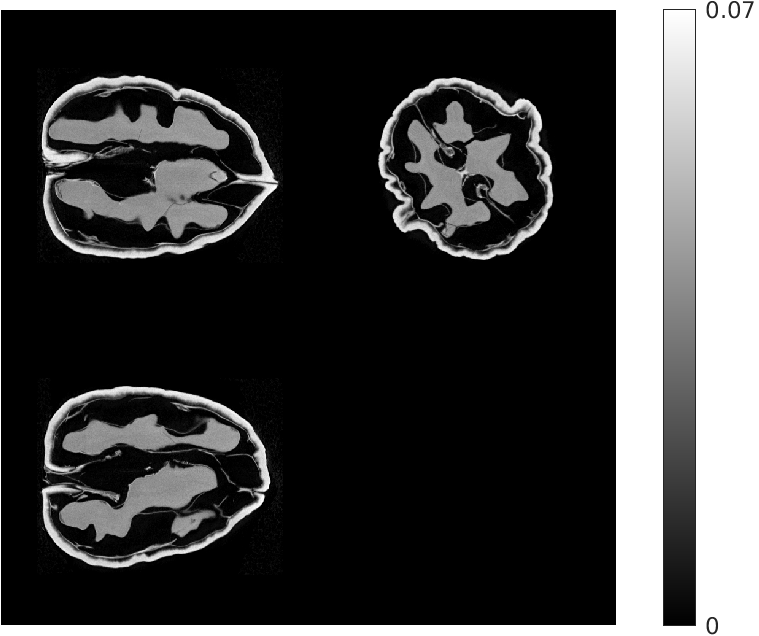

Fig. 3 compares the reconstructions from 4 views. The quality of the reconstruction is poorer compared to that using 8 views, though the proposed approach still visibly outperforms the other methods.

| Ground Truth Test Volume | |

| (a) (NMAE) | |

| FDK | EP Regularized Recon. |

| (b) (1.23) | (c) (0.65) |

| Destreaking CNN | Proposed |

| (d) (0.63) | (e) (0.45) |